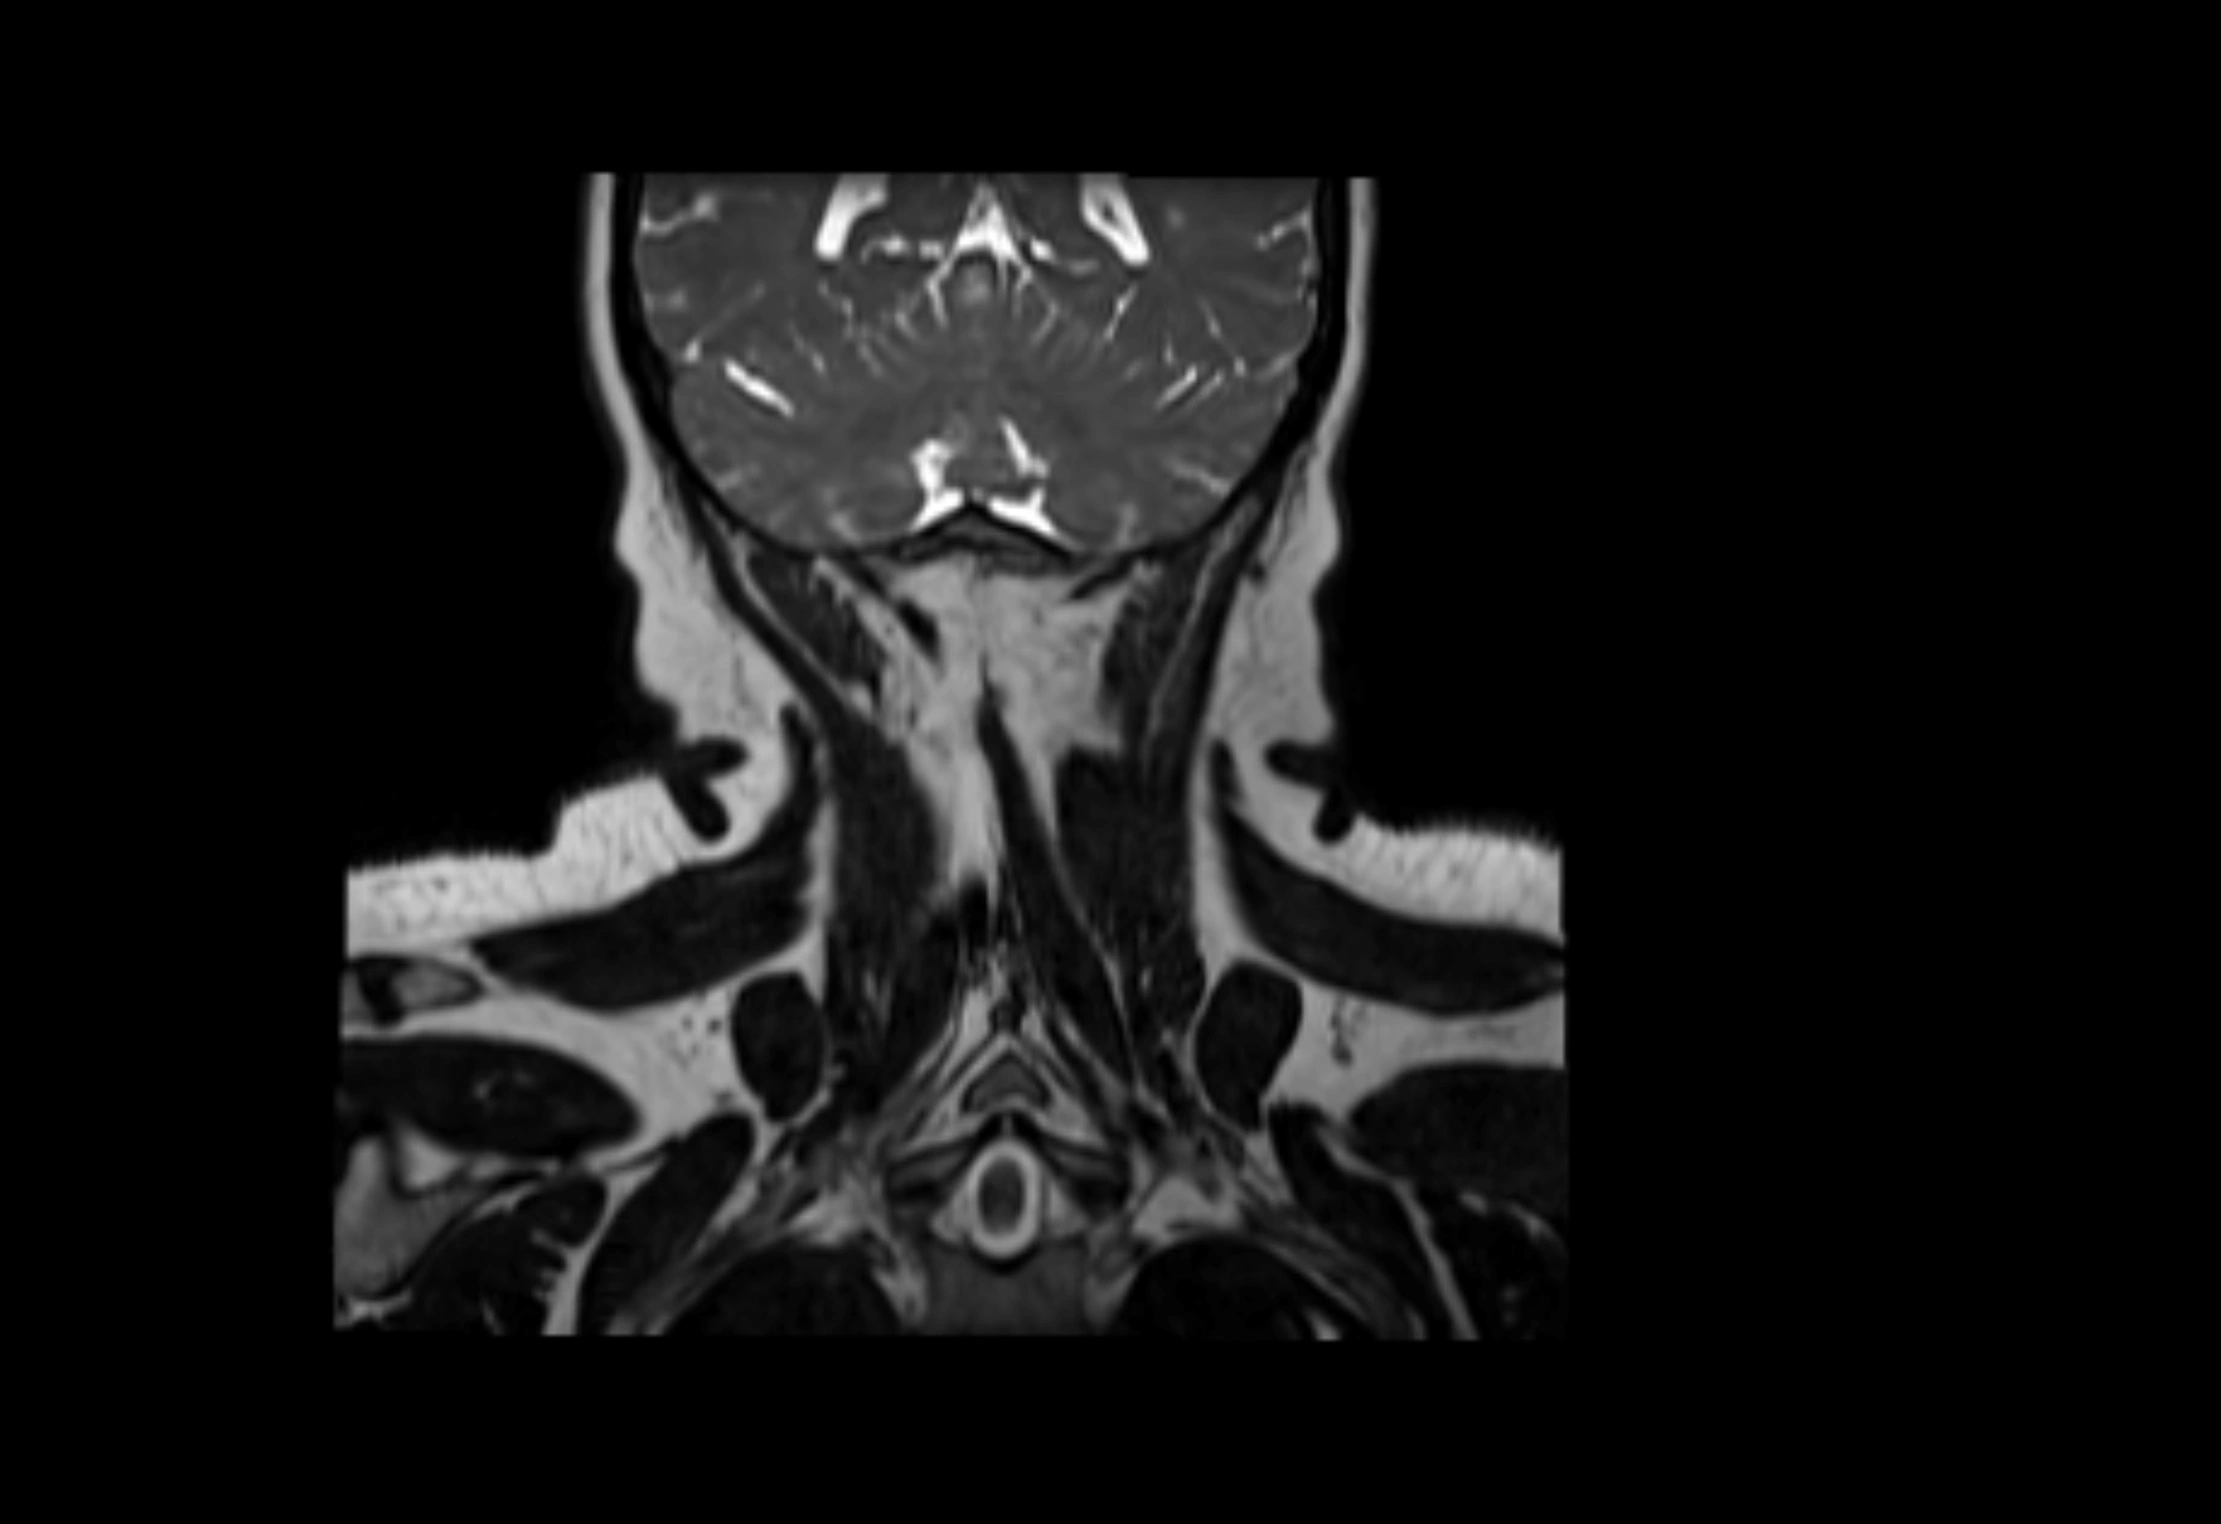

Location

• Found along primary lymph node chains, including preauricular, submandibular, parotid, and occipital regions

• Embedded in subcutaneous fat or superficial fascia, often lateral or posterior to primary nodes

• Variable in number; may occur unilaterally or bilaterally, depending on individual anatomy

MRI Appearance

MRI images

image